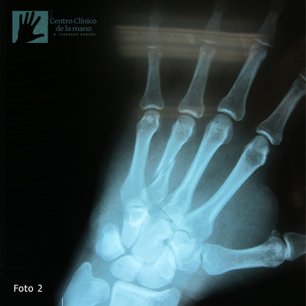

Fractura del Metacarpiano